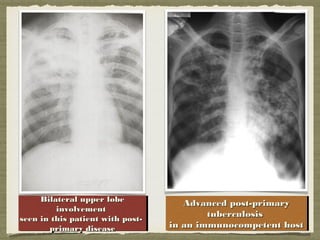

Bilateral upper lobeBilateral upper lobe

involvementinvolvement

seen in this patient with post-seen in this patient with post-

primary diseaseprimary disease

Advanced post-primaryAdvanced post-primary

tuberculosistuberculosis

in an immunocompetent hostin an immunocompetent host